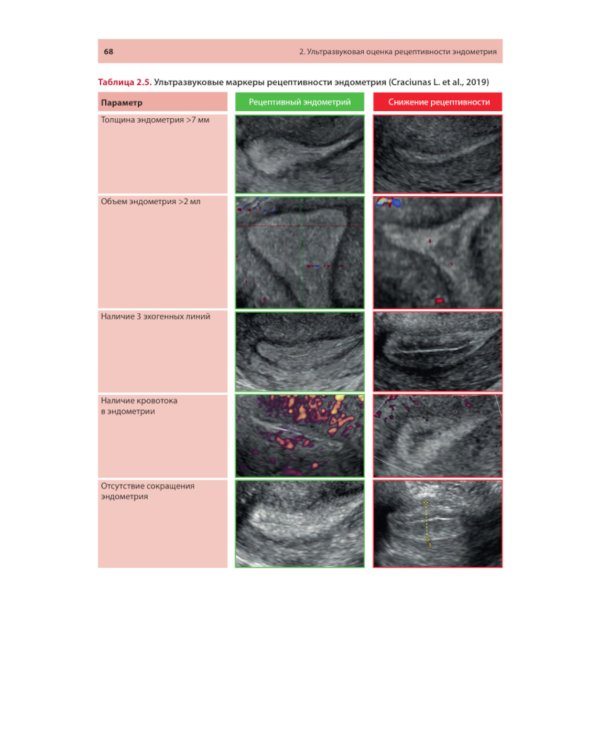

Методические рекомендации освещают современное состояние проблемы ультразвуковой оценки рецептивности эндометрия от общепринятых маркеров до малоизученных, в том числе перспективных, направлений. Описаны ультразвуковые методики, позволяющие оценивать признаки рецептивности в 2D- и 3D-режимах с акцентом на ошибках, которые влияют на интерпретацию результатов. Представлены различные шкалы комплексного анализа. Утверждено в качестве методических рекомендаций для проведения циклов тематического усовершенствования «Ультразвуковая диагностика в гинекологии», общего усовершенствования, ординаторов и аспирантов, проходящих обучение по направлению «Ультразвуковая диагностика, акушерство и гинекология, репродуктология». Протокол Ученого совета ФНМО МИ ФГАОУ ВО РУДН №5 от 16.05.2023.| Издательство | МЕДпресс-информ |